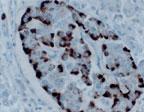

Polyclonal antibody to APAF-1

Fig:1 Formalin-fixed, paraffin-embedded tissue section of human pancreatic islets stained for Apaf 1 using 20-1003 at 1:2000. Hematoxylin-eosin counterstain.

WB: 1:1000-1:2000, IHC (paraffin): 1:1000-1:5000, IHC (frozen): Users should optimize, IP: 1:50-1:200